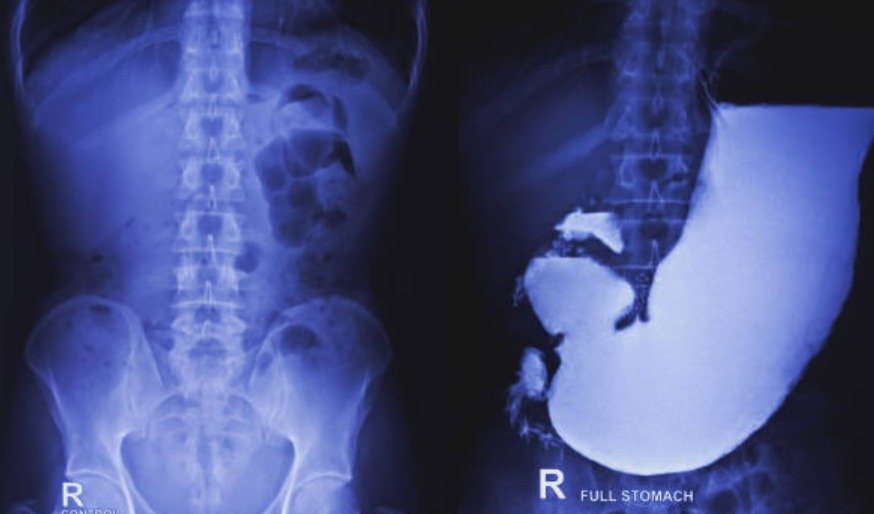

Barium Meal and Follow Through

Imaging of the stomach and small intestine using barium sulfate

Drink barium solution, take X-rays at intervals, procedure can take several hours.

Diagnose blockages, Crohn’s disease, tumors, ulcers in the stomach and small intestine.

Comprehensive view of the stomach and small intestine, aids in diagnosing GI disorders.